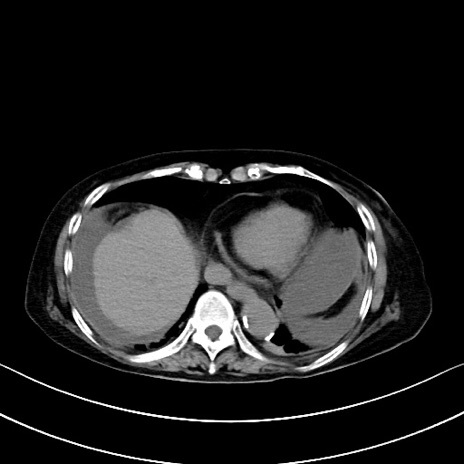

横断像

冠状断像

矢状断像